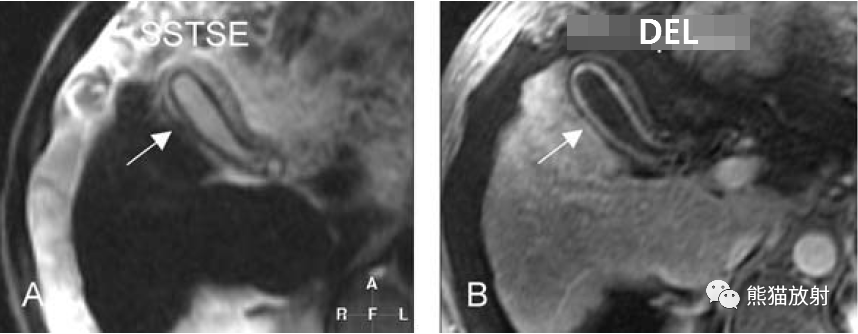

膽囊癌。A~D圖:上方層面,表現如上所述,形成腫物侵及肝臟。E、F圖:下方層面示膽囊壁不規則增厚,明顯不均質強化。

T2壓脂(T2 fatsat):膽囊窩內膽囊癌病變較肝臟為高信號,病變頂部向肝內擴展;

T1同相位(T1 in-phase):膽囊癌病變較肝臟為低信號;

增強動脈期(ART):不均質強化;

延遲期(DEL):部分廓清,部分持續強化。